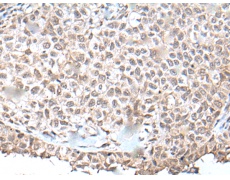

IHC positive control:

Human ovarian cancer and human tonsil